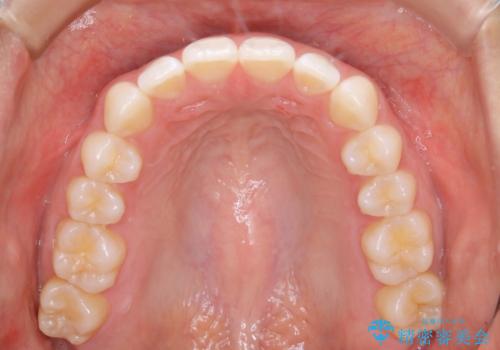

インビザライン矯正 前歯のすきっ歯を治したい

- 上顎の前歯のすきっ歯を治したいとのことで来院されました。

前歯の隙間を閉じる矯正治療の場合、インビザライン適用症例のためインビザラインによる治療をご提案しました。

後戻り防止のため、上唇小帯切除も併用しています。

上唇と歯ぐきを結ぶひも(上唇小帯)が長いと、前歯に隙間が空いてしまうことがあります。今回は隙間を確実に閉じる目的、また矯正後に再び隙間が空かないように、上唇小帯の切除も行っています。